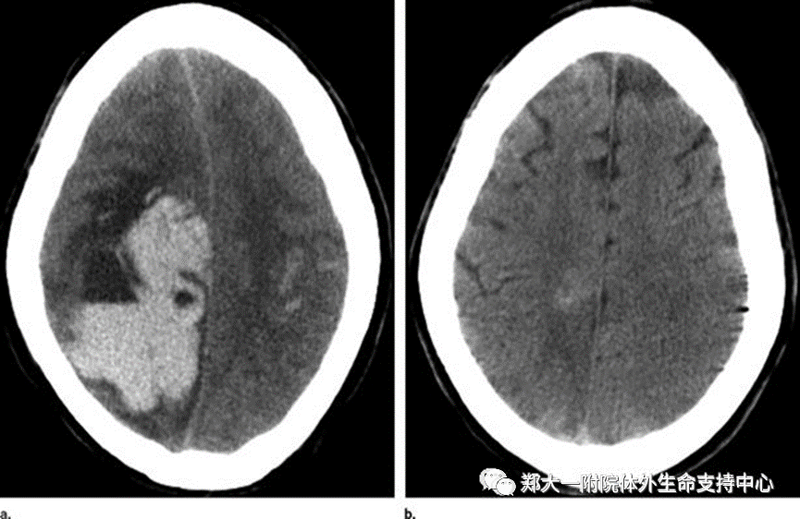

出血:由于患者在ECMO时需要使用血液抗凝药物,患者可在身体的不同部位出现出血。如果出血发生在他们的大脑、肺、胃部或插管处,这会引起非常严重的问题。医疗团队应定时进行体格检查和监测化验指标以确保没有出血。如果有出血,可考虑使用一些止血药。而有时则需要外科干预止血处理。血细胞计数过低时则给予输血或成分血(如血小板)治疗。

脑卒中:在ECMO患者中,大脑的某些区域可能会因为小血栓而导致供血不足。这会导致中风,大脑的某些部分功能可能会永久损伤。大脑损伤的区域决定了一个人中风后会有什么症状。有些病人可能无法移动身体的某些部位,可能有视觉障碍、记忆障碍、失语、读写障碍。有时患者中风后仍会恢复一些功能,但情况并非总是如此。幸运的是,中风非常罕见,患者运行ECMO过程中只有不到5%的几率会发生。